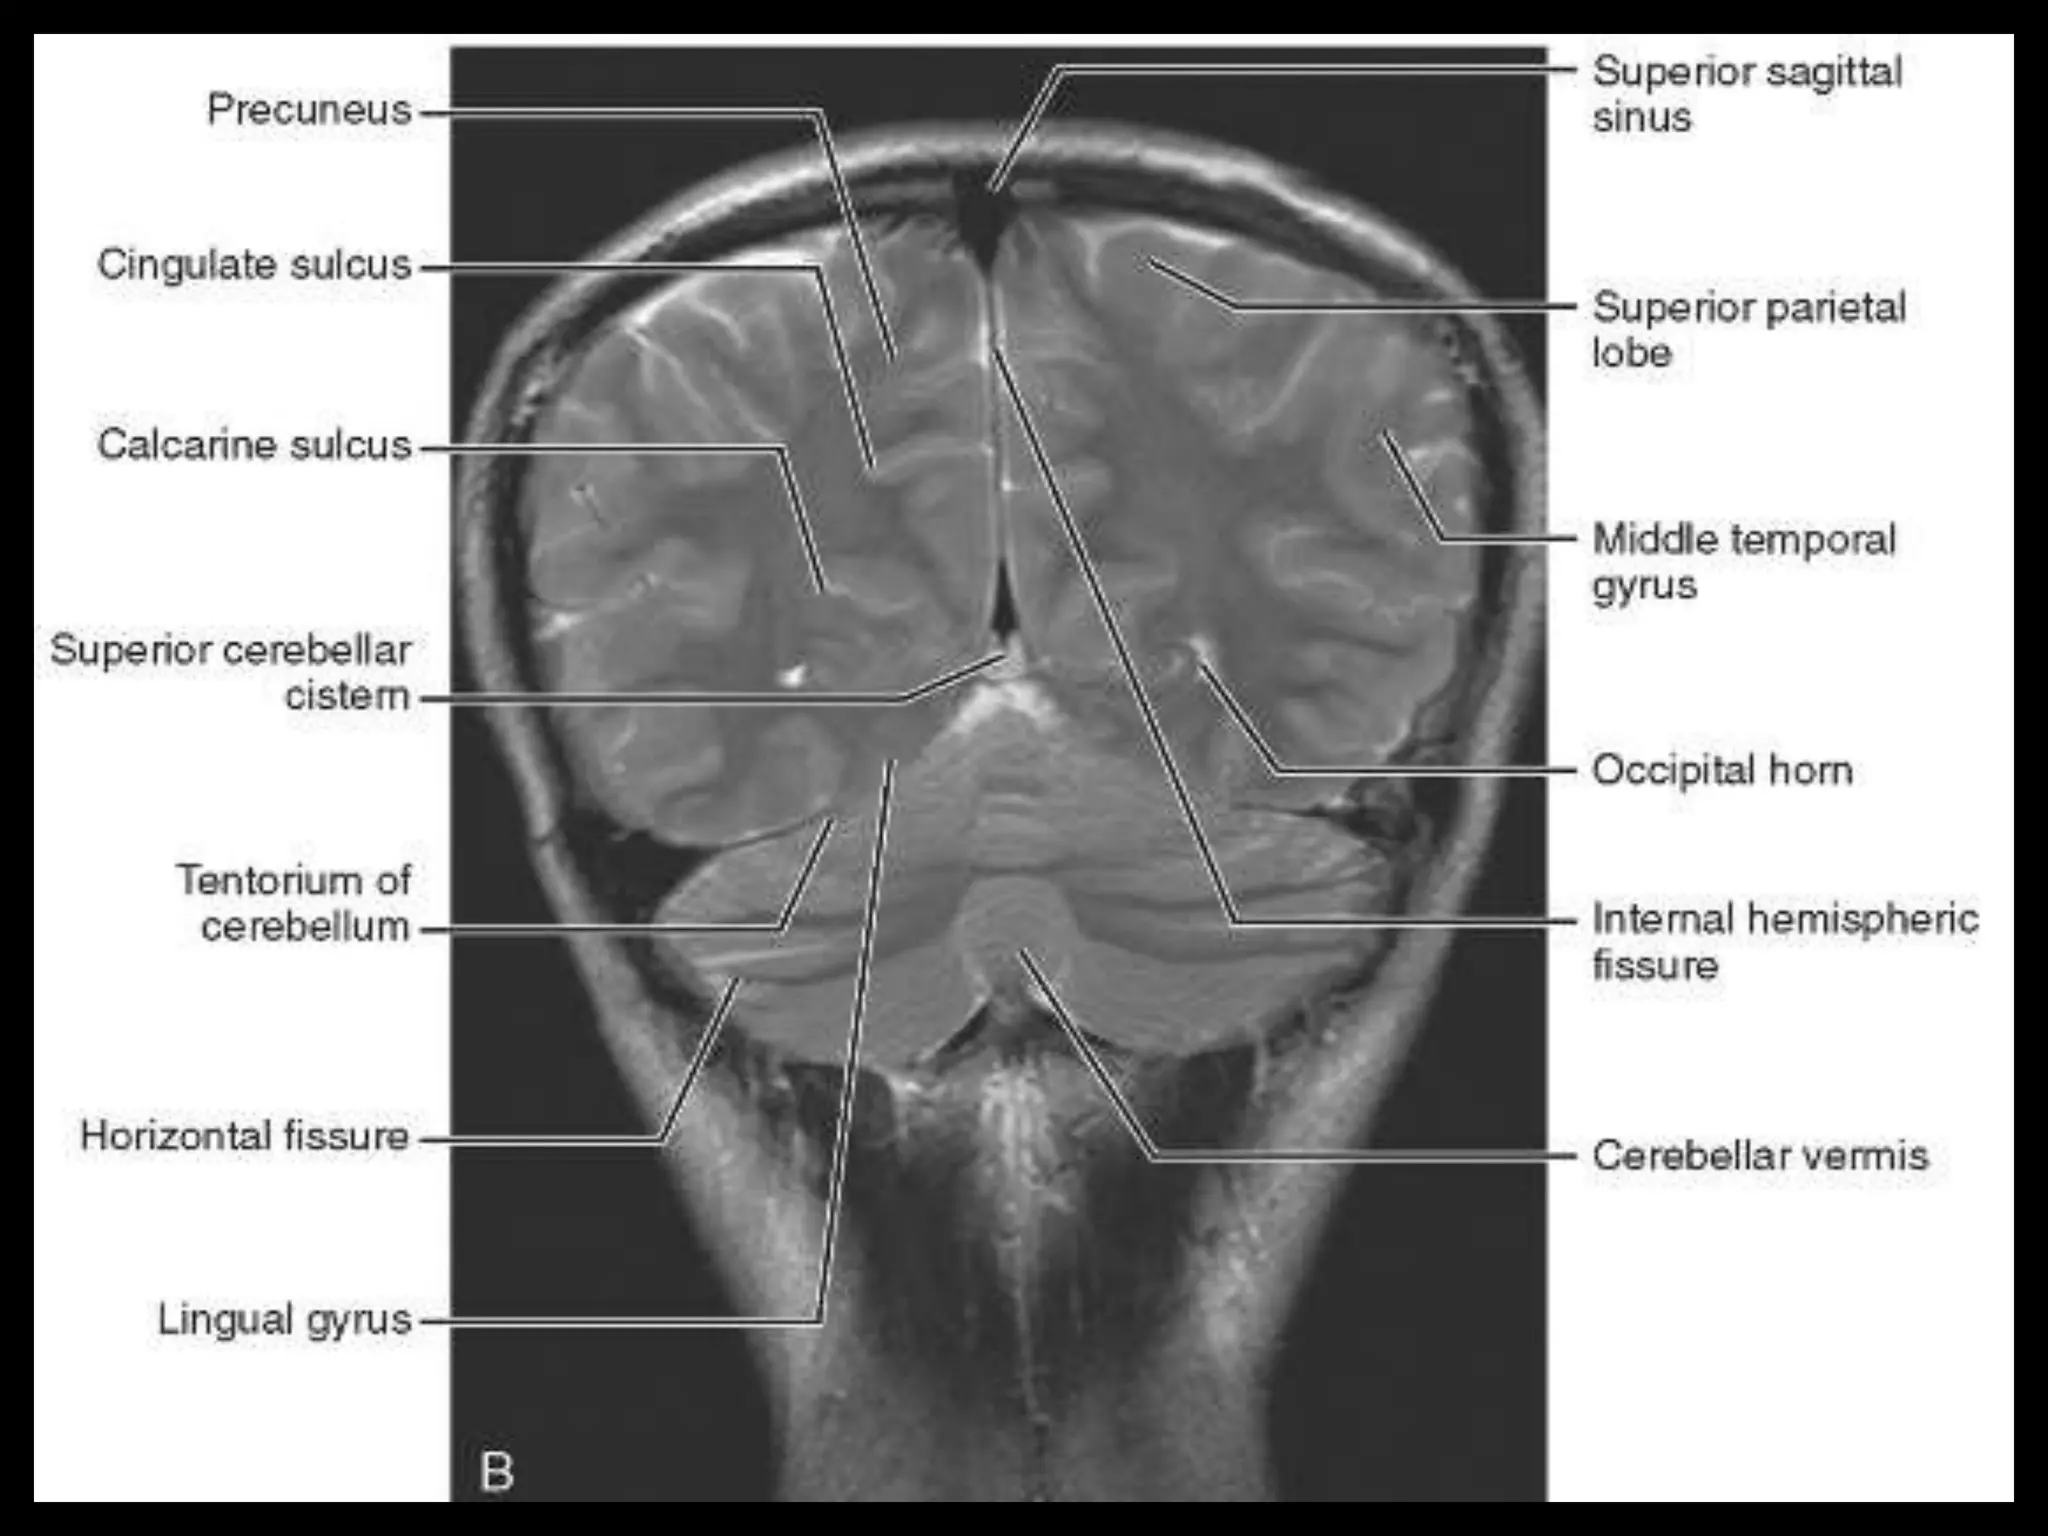

On CT and MR scans, the brain has been briefly viewed in

infratentorial and supratentorial sections, as described below.

with 6-mm slice thickness. Using the sagittal view, the coronal

sections are acquired parallel to the brain stem, and the

sagittal sections are obtained perpendicular to the axial

Sectional Anatomy: NormalAxial CT and MRI Anatomy. On CT and MR scans, the brain has been briefly viewed in infratentorial and supratentorial sections, as described below. CT scans are performed with a 15- to 20-degree angulation to the canthomeatal line at 8-mm increments. MRI scans are generally obtained parallel to the AC-PC line in the axial plane with 6-mm slice thickness. Using the sagittal view, the coronal sections are acquired parallel to the brain stem, and the sagittal sections are obtained perpendicular to the axial section. On MRI studies, cranial nerves IX and X can be demonstrated at this level because they emerge from the postolivary sulcus. The posterior aspect of the cerebellar hemispheres is outlined by the inferior portion of the cisterna magna.